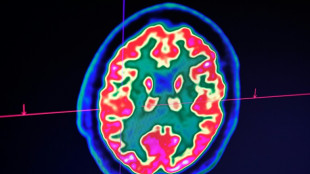

Rare mais fatal, le gliome infiltrant du tronc cérébral est l'une des formes les plus redoutables des cancers du cerveau pédiatriques. Un enfant, pourtant, semble défier les statistiques: sa guérison, unique au monde, suscite aujourd'hui de grands espoirs pour la recherche.